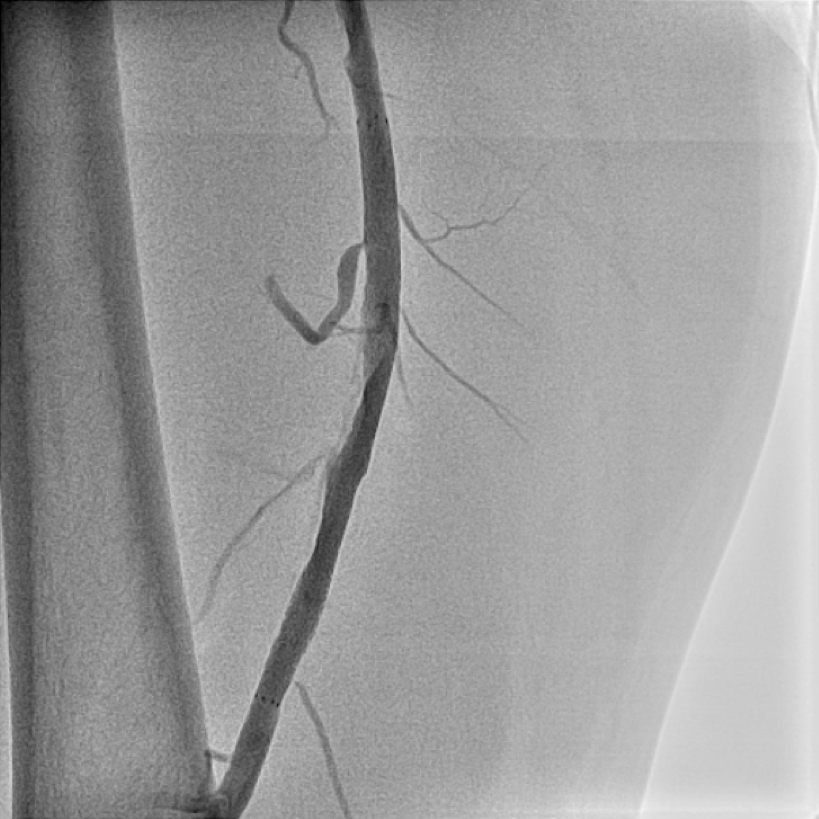

治療には、薬物治療、運動療法、カテーテル治療、バイパス手術、血管新生療法などがありますが、短期間の入院で血流の改善が望めるカテーテル治療は患者負担と治療効果の面から優れた治療法と言えます。(図5、6)

【図5】下肢造影カテーテル検査 カテーテルによる血管造影検査ですが、CT検査 同様に閉塞していることがわかります。